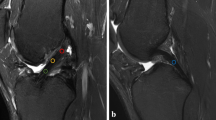

On MRI examination, the T1rho sequence was able to visualize tendinous portions of the AMB and PLB more clearly than the T2 map sequence in gray-scale images, and easily segregated the purely tendinous portion from surrounding synovial tissue (Fig. 1). Color-coded images were capable of visualizing the tendinous portion of the graft in both sequences. Mean T1rho values gradually decreased during the first year after ACL reconstruction (Fig. 2). Such trends were more prominent in AMB than in PLB. In contrast, reduction of T2 map values was dull in both AMB and PLB during the first year. When temporal changes were individually focused, T1rho values decreased more consistently among patients than T2 map values (Fig. 3).

Correlation analysis revealed that T1rho values of both AMB and PLB at 1 year correlated significantly with anteroposterior laxity at 2 and 4 years (Table 3; Fig. 4). However, neither bundle demonstrated significant correlations between T1rho value and rate of positive pivot shift test at 4 year. At the same time, T2 map values of both AMB and PLB demonstrated a significant correlation with anteroposterior laxity at both 2 and 4 years and pivot shift test results at 4 years. Both T1rho and T2 map values failed to exhibit significant correlations with arthroscopic evaluations of actual graft tension, which was commonly seen for both AMB and PLB.

Hypervascularity of the synovial membrane at 3–6 months may increase mean graft signals in the axial plane, which may obscure signals from the tendinous portion of the graft. This might be the case with the PDWI sequence, which has been perceived as a common sequence for not only cartilage, but also ACL. Although no significant differences were identified, T2 map values of PLB appear to increase from 3 to 6 months postoperatively and decrease thereafter, resembling the temporal pattern of conventional T2, PDWI, and gradient echo T2 sequences reported by previous studies [28, 30, 31]. This may suggest that PLB maturation was abrogated or that segregation of the purely tendinous portion from the surrounding synovium was difficult with the T2 map sequence. Ntoulia et al. assessed temporal changes in graft signals using Gd-DTPA and concluded that synovial tissue embracing the graft continued to display high intensity throughout the course of graft maturation, whereas the volume of synovial tissue peaked at 6 months and decreased until 12 months [9]. The peak graft intensity at 6 months documented in numerous past studies using conventional sequences may be attributable to an increased volume of synovial tissue. Jansson et al. proposed the same insight, that periligamentous tissue surrounding the graft largely contributed to increased graft intensity at 6 months postoperatively [32]. Detection of signals from the purely tendinous portion of the graft is important for proper assessment of graft maturation. In the present analysis with T1rho sequence, ROIs were easily set in the purely tendinous portion of AMB and PLB without color coding images, achieving substantial segregation from surrounding synovial tissue.